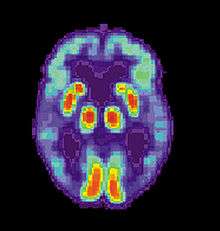

PET scan of the brain of a person with AD showing a loss of function in the temporal lobe

Alzheimer's disease is usually diagnosed based on the person's medical history, history from relatives, and behavioural observations. The presence of characteristic neurological and neuropsychological features and the absence of alternative conditions is supportive.[104][105] Advanced medical imaging with computed tomography (CT) or magnetic resonance imaging (MRI), and with single-photon emission computed tomography (SPECT) or positron emission tomography (PET) can be used to help exclude other cerebral pathology or subtypes of dementia.[106] Moreover, it may predict conversion from prodromal stages (mild cognitive impairment) to Alzheimer's disease.[107]